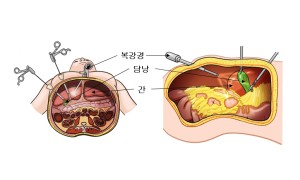

치료

일반적으로 석회화 담낭 환자의 약 2~3%에게 담낭암이 동반됩니다. 일부 연구에 따르면 15%까지 나타난다고 보고되기도 합니다. 따라서 석회화 담낭의 증상이 없거나, 담석이 없다고 하더라도 발견 즉시 담낭 절제술을 시행하여야 합니다.